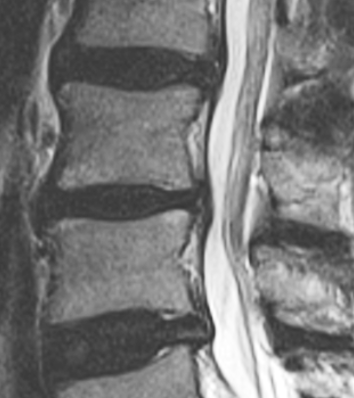

- U rizikových stavů (velké výhřezy, neurologie) – vždy kombinovat s vyšetřením, MR, konzultací s neurochirurgem / ortopedem.

Vědecké okénko: biomechanika tlaku v disku, „dekomprese“ a co z toho plyne

Traction / „dekomprese“ – co víme a co ne:

Open-access – Cochrane 2013. PMC - Chow et al. (2017): Horizontální trakce ~42 % tělesné hmotnosti → krátkodobé zvětšení výšky disku (hlavně posteriorně) na MRI; malá studie.

PubMed – Medicine 2020. PubMed - Chung et al. (2015, MRI v reálném čase): MR vizualizuje okamžité tvarové změny disku během kontinuální trakce, klinický dopad však zůstává sporný.

Měřitelné zvětšení výšky disku se v malých studiích objevuje až při tahech ~40–60 % tělesné hmotnosti a je spíše krátkodobé; celkově však systematické přehledy nepotvrzují klinickou převahu trakce jako samostatné metody. Rozumný mechanismus úlevy je redistribuce sil přes lepší motorickou kontrolu (transversus, multifidi) a dávkovaný pohyb, ne „zvednutí ploténky“. PubMed+3PubMed+3